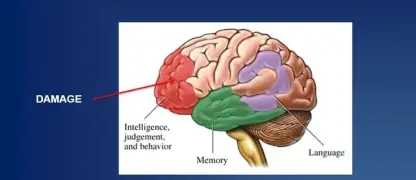

- Early CTE symptoms can include behavioral changes, such as impulsivity, depression, mood swings, and paranoia, which may appear years after the head trauma occurred.

- As the disease progresses, cognitive impairment becomes more pronounced, with individuals experiencing significant memory loss, confusion, and impaired judgment, which can resemble Alzheimer's disease.

- In later stages, motor symptoms may develop, including tremors, slowed movement (parkinsonism), and difficulty with speech and swallowing, reflecting widespread brain damage.

Visualizing concepts related to CTE